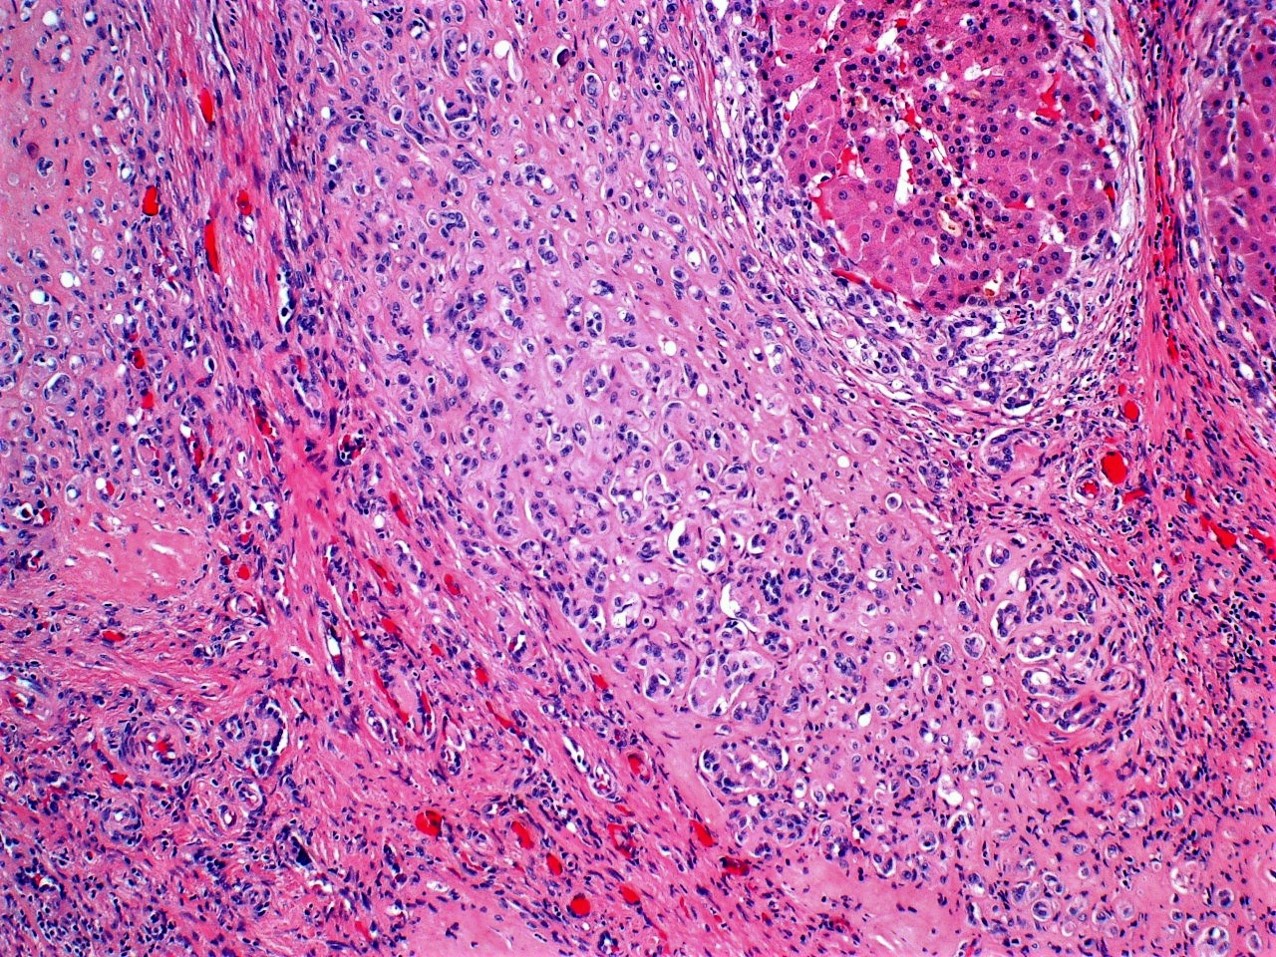

A 21-year-old man presented with a clinical history of cryptogenic cirrhosis. Grossly, the explant liver was noted to be very firm. Sectioning revealed parenchymal color varying from dark red to tan white with dilated ducts and apparent stones. No discrete lesion was identified. Histologic examination revealed numerous partially involuted hepatic regenerative nodules often surrounded by swaths of gland-like tissue, the lumens of some showing calcifications and occasional red blood cells. Cytologically, no increased mitoses or necrosis were noted. Immunostains showed these areas to be positive for CD34, CD31, and negative for CDX2 and CA 19.9.

What chromosomal translocation is this tumor associated with?

Answer: B.) t(1;3)(p36.3;q25), CAMTA1- WWTR1